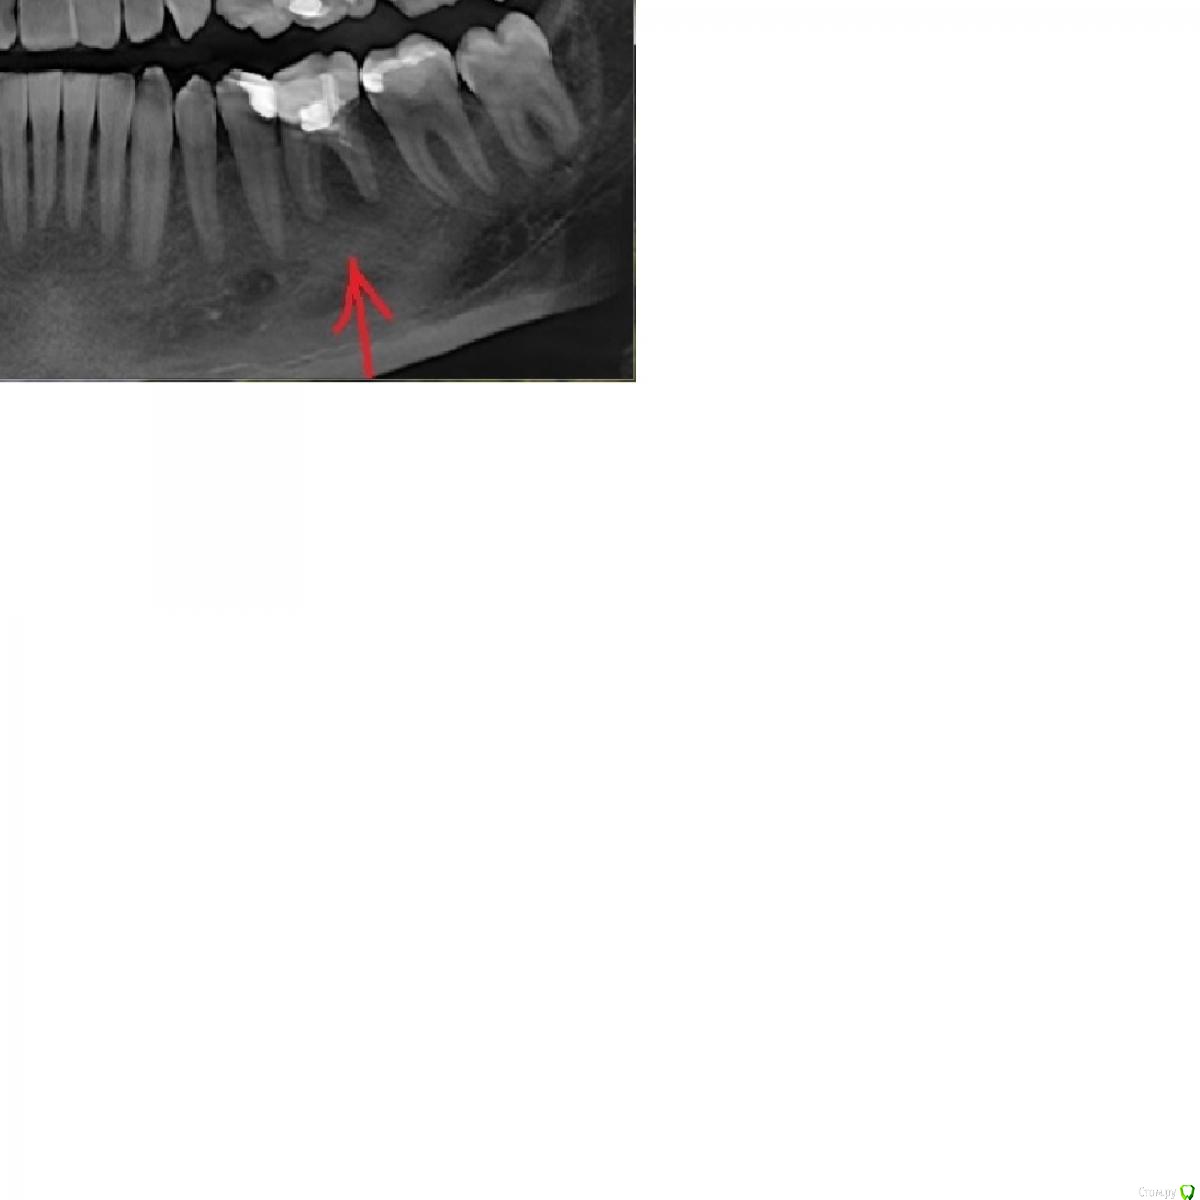

константинgh Опубликовано 17 ноября, 2016 Поделиться Опубликовано 17 ноября, 2016 (изменено) врач сказал, что надо удалять но насмотревшись роликов на youtube понял, что даже самую сложную кисту можно вылечить (можеть быть сложно, но все-таки лучше чем имплант)и еще такой момент записали на диск снимок но открывается лишь изображение в левом верхнем углу нет 3D изображения Изменено 17 ноября, 2016 пользователем константинgh Ссылка на комментарий

DmitrySH Опубликовано 17 ноября, 2016 Поделиться Опубликовано 17 ноября, 2016 Снимок мелковат. Попробуйте сделать крупнее. 1 Ссылка на комментарий

dok1 Опубликовано 18 ноября, 2016 Поделиться Опубликовано 18 ноября, 2016 Всё же склоняюсь к удалению. Позже имплант. 1 Ссылка на комментарий

константинgh Опубликовано 18 ноября, 2016 Автор Поделиться Опубликовано 18 ноября, 2016 (изменено) Всё же склоняюсь к удалению. Позже имплант.то есть совсем все плохо, просто видел как безнадежный зуб удавалось спасти объясните как обычному человеку какие все такие есть варианты леченияможет дело в мастерстве врача, просто не все берутся за сложные случаи и не дают 100% гарантии, но все же это шанс, а не удаление Изменено 18 ноября, 2016 пользователем константинgh Ссылка на комментарий

Доктор Хаус Опубликовано 18 ноября, 2016 Поделиться Опубликовано 18 ноября, 2016 (изменено) Не вкладывайте средства в не надежные способы лечения этого зуба. Имплантация самый надежный и прогнозируемый способ восстановления утраченного зуба. Изменено 18 ноября, 2016 пользователем Доктор Хаус Ссылка на комментарий